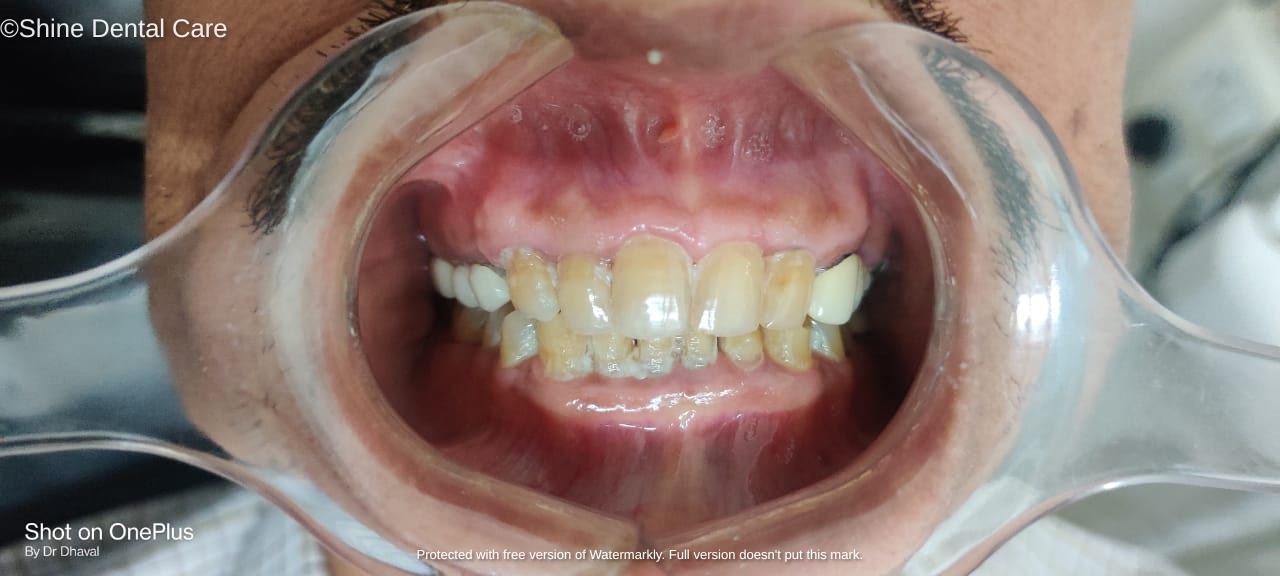

Full Mouth Rehabilitation

As the name implies, Full Mouth Rehabilitation refers to rebuilding and/or replacing all of the teeth ina patient’s mouth. Full Mouth Rehabilitations combine esthetics with the science of restorative dentistry to improve the health, function, and beauty of the mouth.

The treatments can include onlays, crowns, bridges, veneers, dental implants, and/or dentures that will essentially provide not only a "'smile makeover", but improved chewing efficiency for the patient. In some patients, other specialties will orthodontics may also be employed to facilitate the best possible outcome.